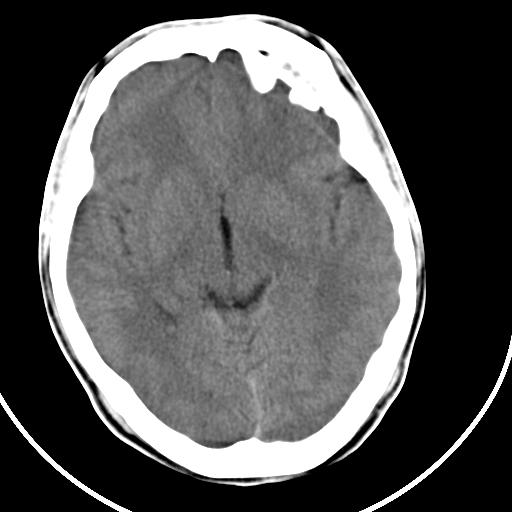

标题: CT21939:男20岁,外伤一年后,现头疼. [打印本页]

标题: CT21939:男20岁,外伤一年后,现头疼.

硬膜外血肿机化

硬膜外血肿伴包膜钙化

左侧额部硬膜外血肿机化、骨化。

颅内的贝壳就是这样形成的。

左侧额部硬膜外血肿机化、骨化